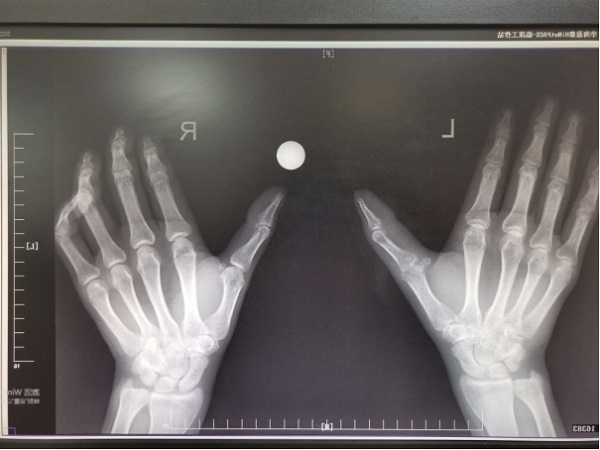

在生活中,有很多中老年人長(zhǎng)期受類風(fēng)濕性關(guān)節(jié)炎困擾,掌指關(guān)節(jié),指間關(guān)節(jié),趾趾關(guān)節(jié),趾間關(guān)節(jié)這樣的“小”關(guān)節(jié)是主要侵襲對(duì)象。受累以后,手指或足趾關(guān)節(jié)增粗變形,反復(fù)疼痛、活動(dòng)受限,很多病人深受折磨。 近期,二...